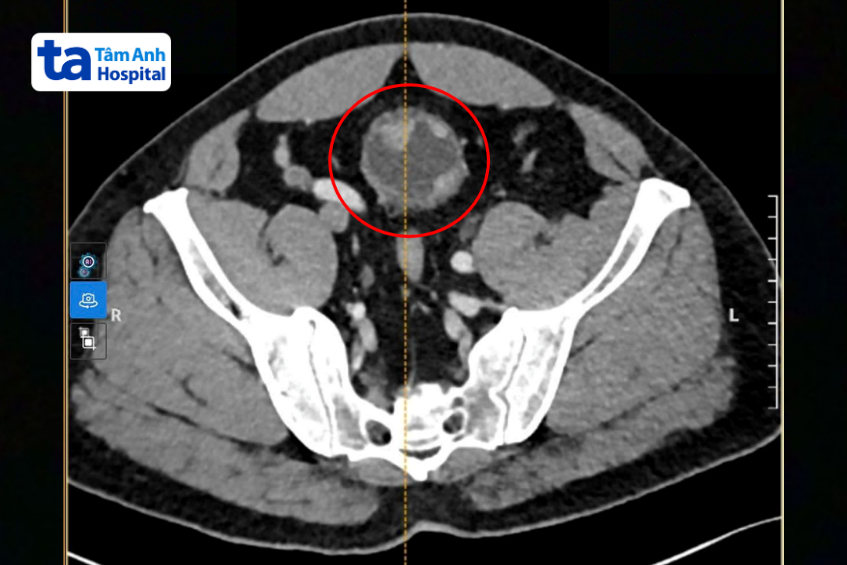

Khi đến khám tại Bệnh viện Đa khoa Tâm Anh TP HCM, bác sĩ siêu âm và nội soi bàng quang phát hiện khối u có đường kính khoảng 4-6 cm. Kết quả sinh thiết xác định u ác tính và đã có dấu hiệu xâm lấn vào lớp cơ bàng quang.

Hình ảnh CT ghi nhận khối u to bất thường xâm lấn cơ bàng quang người bệnh. Ảnh: Bệnh viện Đa khoa Tâm Anh

Hình ảnh CT ghi nhận khối u to bất thường xâm lấn cơ bàng quang người bệnh. Ảnh: Bệnh viện Đa khoa Tâm Anh